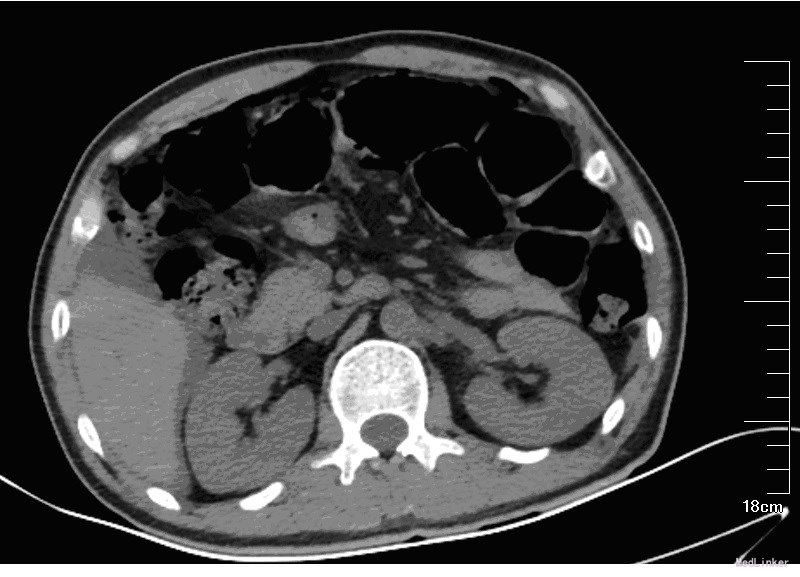

入院后,化验:血常规:白细胞:15600/mm3,嗜酸性粒细胞分数:20.3%; ESR 69 mm, CRP 176 mg/l,风湿因子:656 UI/ml,pANCA antibodies 阳性. 行肺CT:见双肺多发呈类圆形内部稍低密度影,大小不一,较大者约3.2*2.6cm(图1)。考虑肺泡出血和嗜酸性粒细胞侵润。鼻黏膜活检病理证明大量嗜酸性粒细胞侵润。根据上述,诊断为嗜酸性肉芽肿性多血管炎(EGPA,eosinphilic granulomatosis with polyangiitis)。予激素和免疫抑制剂等对症治疗。患者激素减量过程中出现咳血反复,周身及肛周出现溃疡破溃,再次与甲强龙500mg冲击后症状缓解,口腔及肛周、下肢溃烂均较前好转。进食软食一天后突然出现腹痛、发热,腹膜炎症状,查体:全腹压痛,以下腹部为重,伴有反跳痛及肌紧张。完善全腹CT检查考虑消化道穿孔(图2),EGPA并发穿孔的患者行剖腹探查,小肠穿孔修补术。术中见:腹腔小肠肠管明显扩张,多处脓苔,广泛粘连,腹腔内黄绿色渗出100ml,吸尽渗出探查,见距回盲部5cm至距TREITZ韧带150cm之间小肠多发穿孔共11处,较大者破孔3cm*3cm(图3),较小者0.4*0.4cm,予以4-0可吸收线沿肠壁横轴缝合肠壁全层及浆肌层。病理(图4):(小肠穿孔周缘)炎性肉芽组织。术后予以禁食水抗炎补液抑酸及激素治疗。术后6天因血管炎病情反复发作,出现发热,皮肤红斑,7天出现肠瘘,予以双腔套管持续冲洗接负压吸引后逐步愈合后出院。继续风湿免疫科随诊治疗。未有再次发生消化道穿孔。